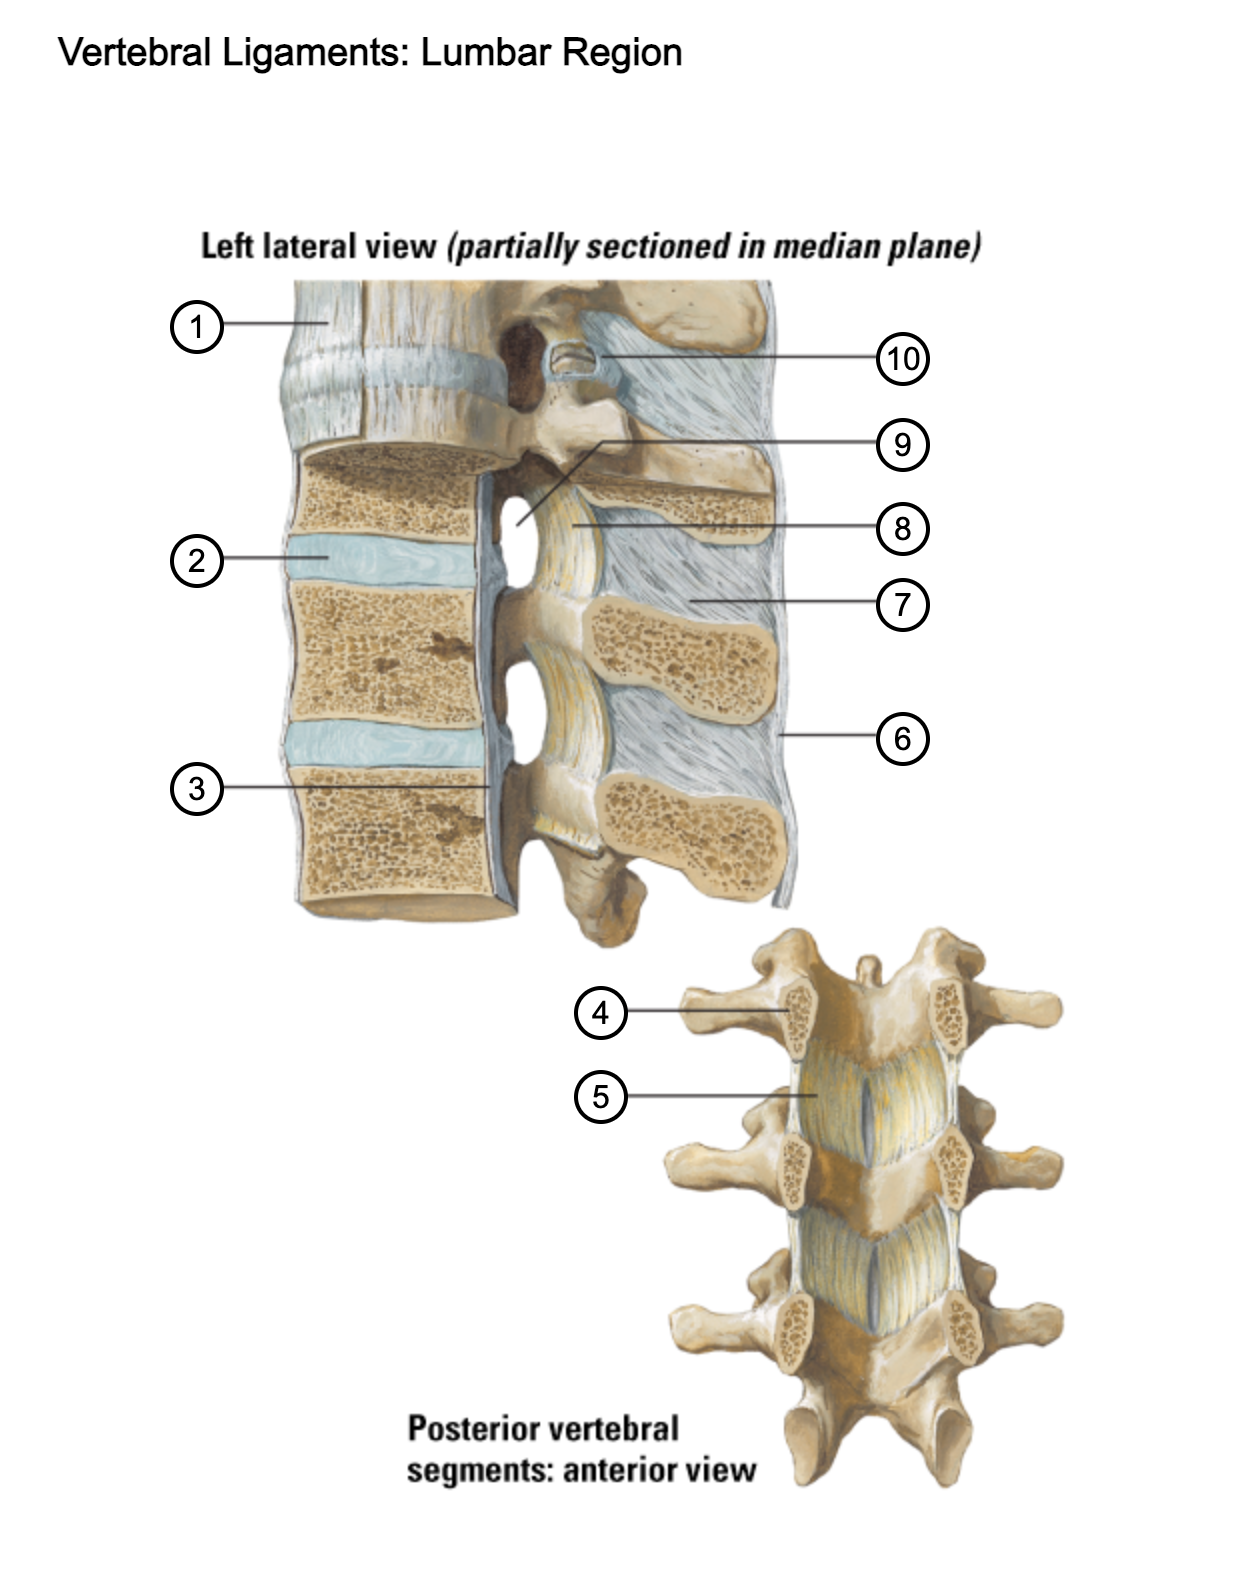

1

anterior longitudinal ligament

2

intervertebral disc

3

posterior longitudinal ligament

4

pedicle (cut surface)

5

ligamentum flavum

6

supraspinous ligament

7

interspinous ligament

8

ligamentum flavum

9

intervertebral foramen

10

capsule of zygapophysial join (partially opened)